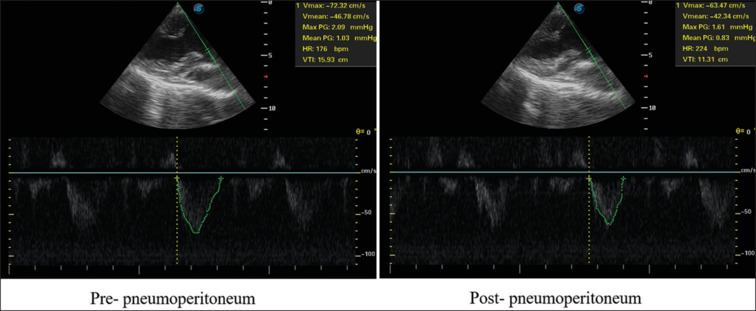

Background: The establishment of pneumoperitoneum has impacts on patient's cardiovascular function. In this study, the respiratory variation of inferior vena cava (IVC), stroke volume (SV) index, and other parameters was monitored to determine how the pneumoperitoneum affects the patient's hemodynamic and acknowledge how to resolve it.

Materials and methods: Fifty-five patients were randomly divided into Group A (8 mmHg), Group B (10 mmHg), Group C (12 mmHg), Group D (14 mmHg), and Group E (12 mmHg, infusion with 7 mL/kg crystalloid solution). The parameters including IVC variability, SV index, mean artery pressure (MAP), heart rate (HR), cardiac output index (CI), and airway pressure were measured, to compare the changes before and after pneumoperitoneum.

Results: Among Group A, Group B, Group C, and Group D, there were no significant differences in patients' prepneumoperitoneum information. Compare with prepneumoperitoneum, the difference in IVC variability, SV index, MAP, HR, CI, and airway pressure was statistically significant (P < 0.05). After the establishment of pneumoperitoneum, the difference in IVC variability, SV index, and airway pressure among Group A, Group B, Group C, and Group D was statistically significant (P < 0.05). Compare with Group C, the change rates of IVC variability, SV index, MAP, HR, and CI were smaller in Group E (P < 0.05).

Conclusion: The establishment of pneumoperitoneum could increase the patient's IVC variability and reduce SV index, and with the increase of pressure, IVC variability had an increasing trend, SV index had a decreasing trend. Fluid transfusion could reduce the relative influence of the pneumoperitoneum.